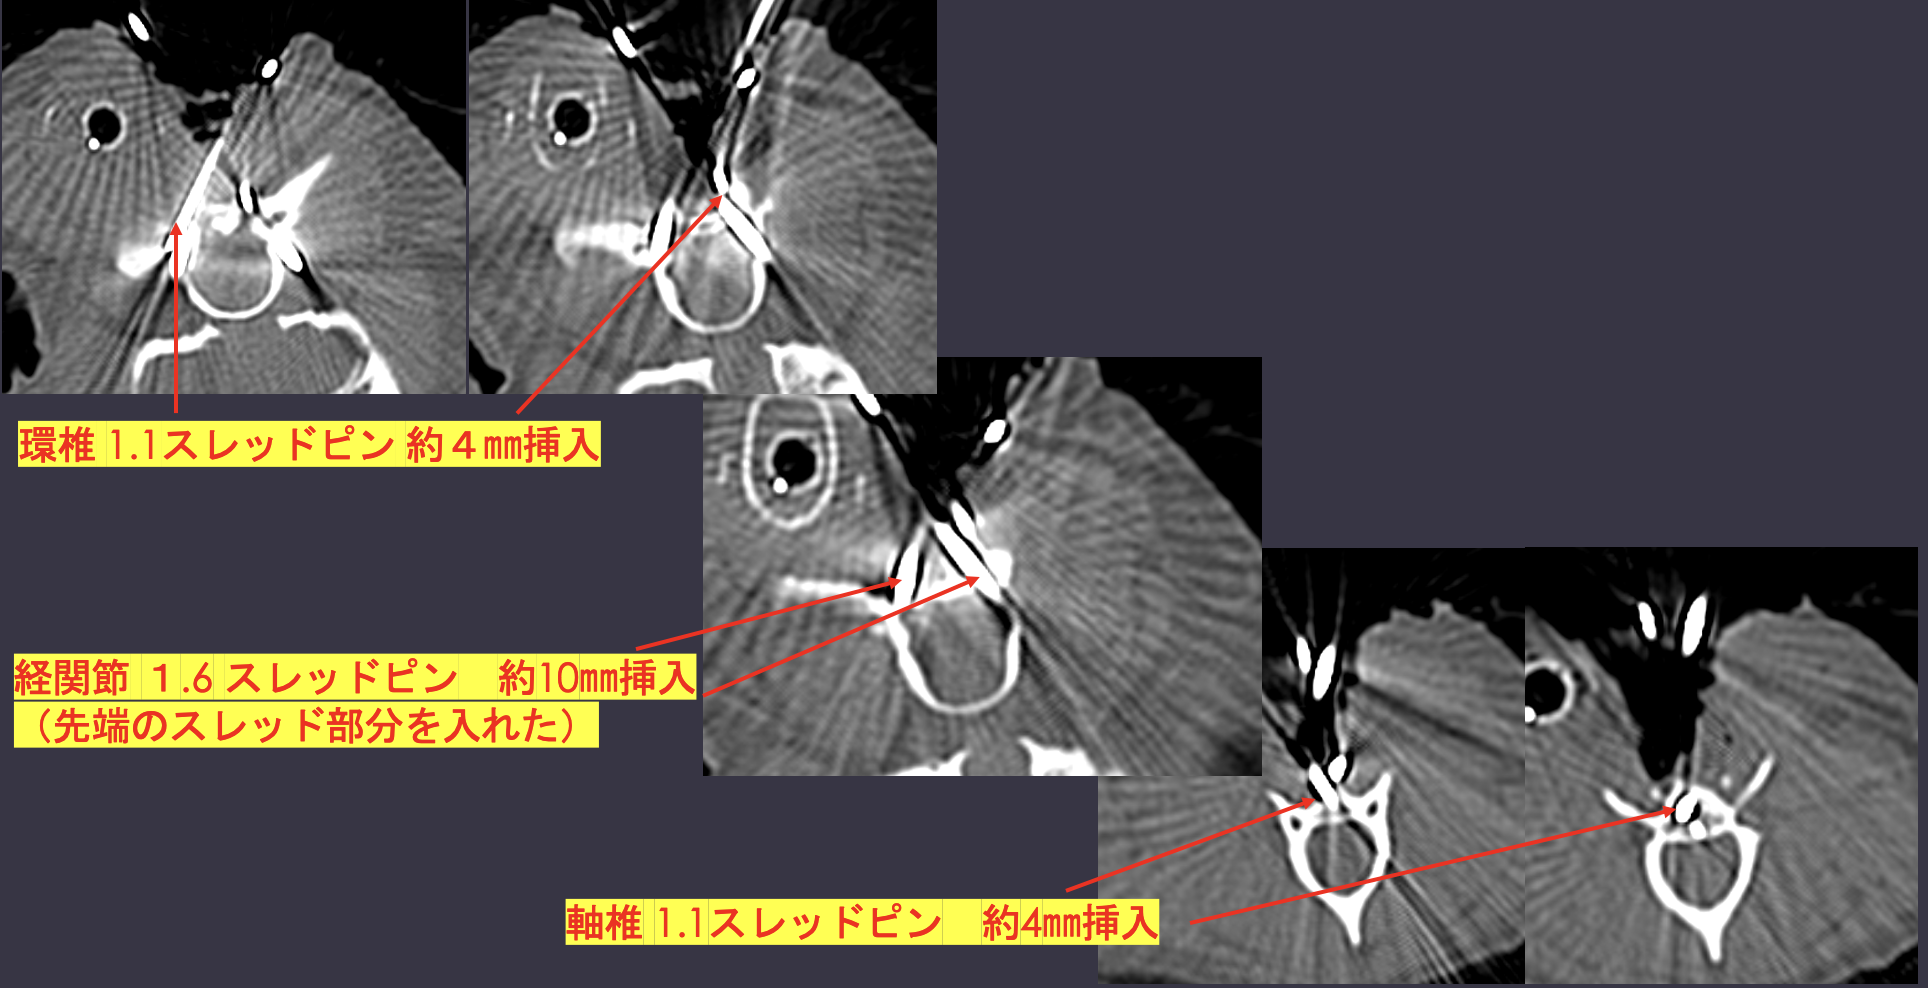

CTより軸椎歯突起の背側変移、MRIよりC1-2領域に脳脊髄液の貯留が認められた

腹側椎体固定術